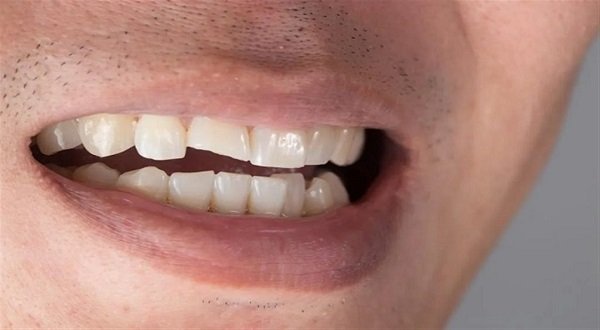

جدول المحتويات تتعرض الأسنان يومياً لعوامل تؤثر على صحتها، لكن ليس كل ضرر سببه التسوس، تعرف معنا في هذا المقال على الفرق بين تسوس وتاكل الاسنان. ما هو تسوس الاسنان؟ هو حالة مرضية تحدث عندما تتعرض الأسنان للتآكل والتلف نتيجة لتراكم البلاك على سطح الأسنان. يحدث التسوس عندما تتحول البكتيريا الموجودة في الفم إلى حمض […]